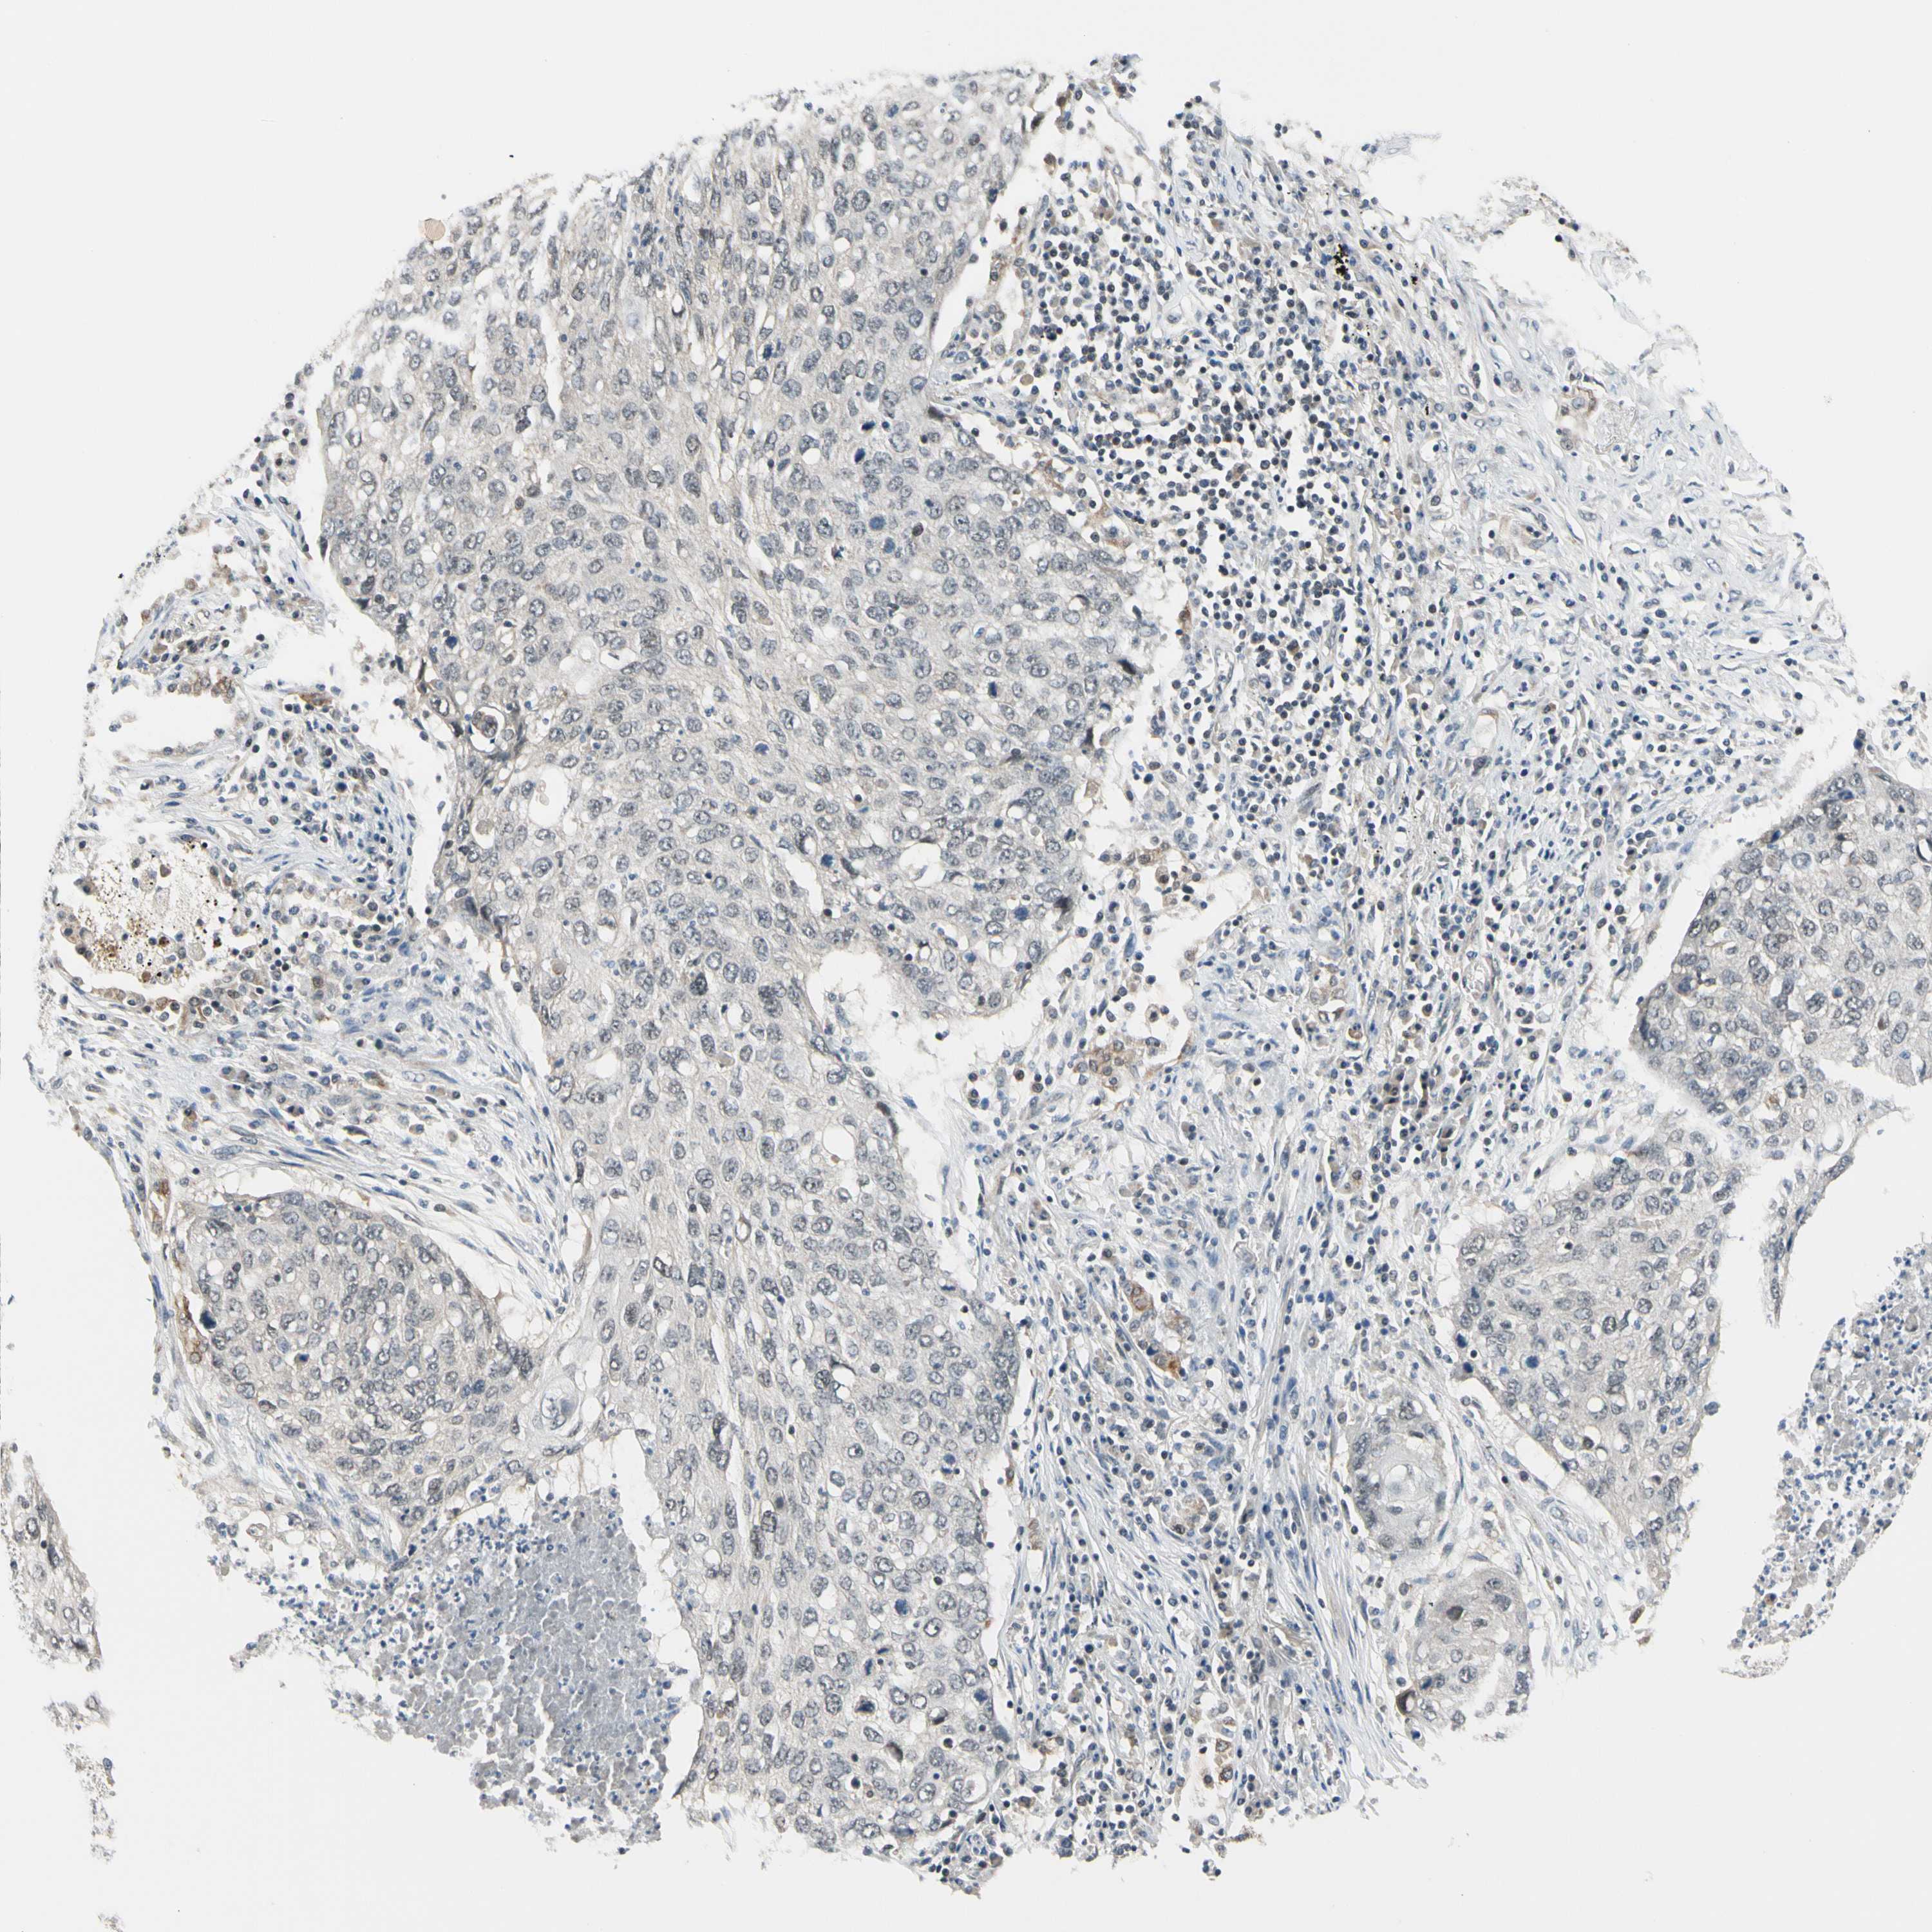

CANCER LUNG CANCER Show tissue menu

LUAD TCGA LUAD VALIDATION LUSC TCGA LUSC VALIDATION PROTEIN LUAD CPTAC PROTEIN LUSC CPTAC PROTEIN EXPRESSION

ANTIBODIES

AND

VALIDATION